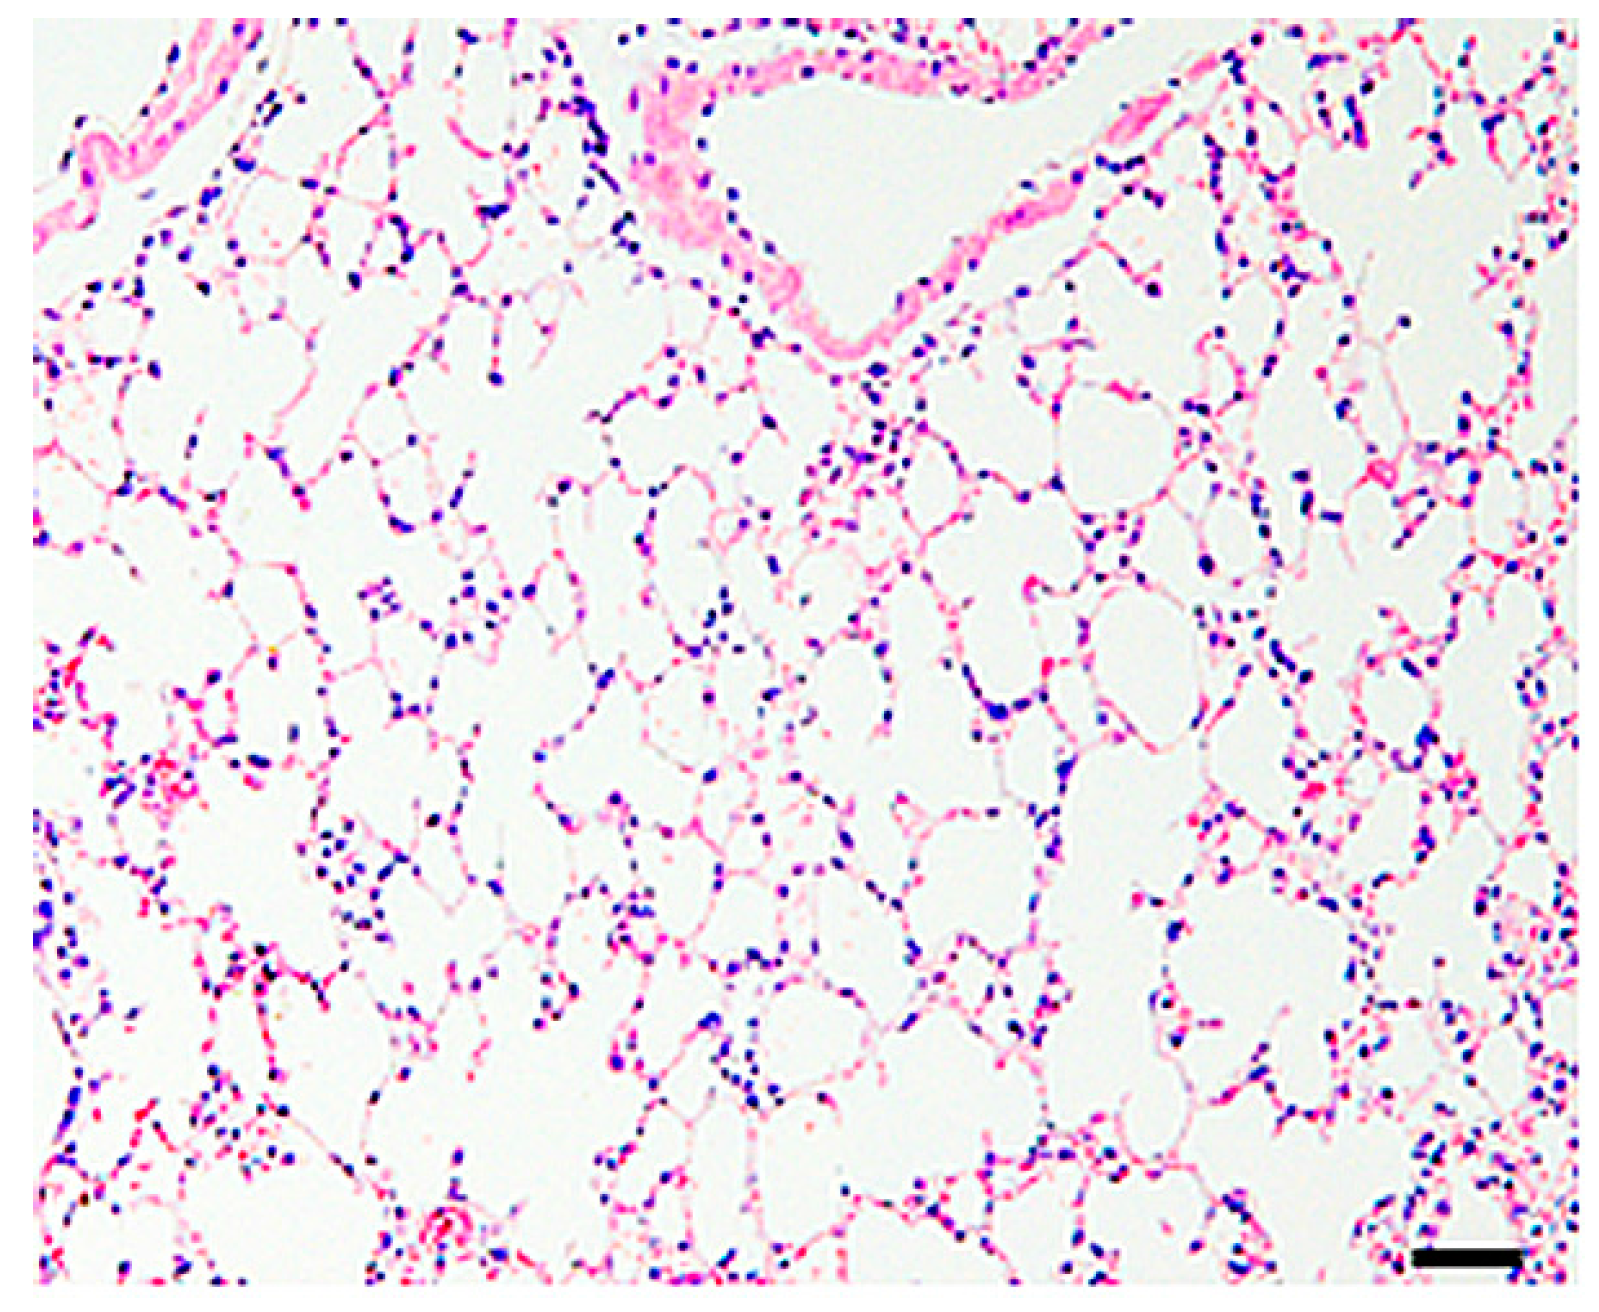

2.2. Histopathology of the Lungs

2.5. Electron Microscopy Analysis